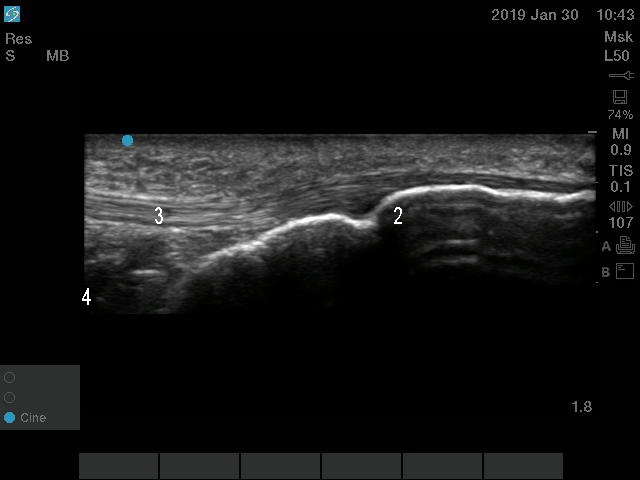

Knee Infrapatellar Tendon Anatomy 2 Image

2. Tibial Tuberosity

3. Patellar Tendon

4. Hoffa’s Fat Pad